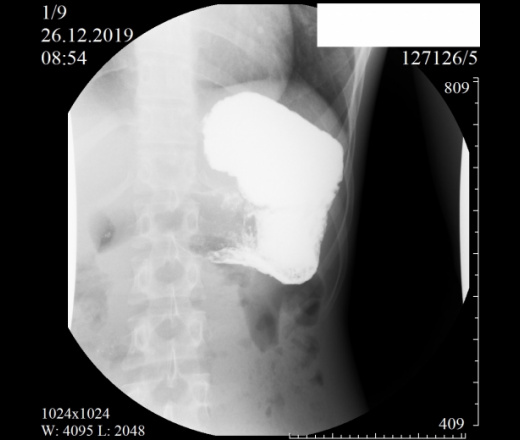

Девочка, 2004 г. Направлена с диагнозом ФНГ печени в онкоцентр. Приложены снимки рентгеноскопии ЖКТ. Помогите с интерпретацией, очень редко с этим работаем. Спасибо.

Как понимать аббревиатуру ФНГ? Не брался бы выность заключение после проведения Rg-скопии желудка, только по представленным снимкам. Можно однозначно сказать, что есть гипотония желудка( некотрые врачи используют термин гастроптоз).

"(красиво начали, жаль, оборвали) - гипотонус желудка, гипотонус луковицы ДПК, вероятный дуодено-гастральный рефлюкс, аорто-мезентериальная компрессия ДПК (стадия 1 или 2, не скажу - недостаточно снимков, скопию закончили рано), птоз тощей кишки и колоноптоз. "©

Многоуважаемые коллеги, я бы усомнился и в проявлениях артериомезентериальной компрессии, так она проявляется в вертикальном положении.